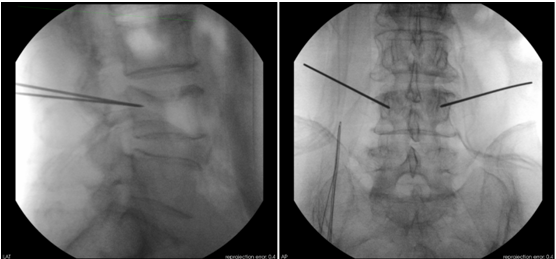

经MRI及CT检查示:腰4椎体压缩性骨折。经专家讨论后,医疗团队拟采用机器人辅助,局麻下行经皮球囊扩张椎体成形术。经过精密的仪器调试和配准,术前进行了反复的模型演练。刘时璋主任团队将患者的CT数据与机器人系统配准,工程师团队将事先规划好的个体化穿刺路径数据植入机器人系统。将术中的正侧位X线透视数据与CT数据融合后,机械臂按照术前规划路径,一次性穿刺成功,位置精准满意。

传统手术徒手穿刺需要在反复透视下,多次调整穿刺位置、方向及深度,增加了患者的不适感,且不一定能够达到理想的穿刺位置。而此例患者在脊柱机器人的辅助下,穿刺针精准地置入骨折塌陷位置,促使球囊扩张复位准确高效。穿刺过程中灵敏的压力反馈系统及可调的穿刺速度,大大增加了穿刺过程的安全性,使传统PKP手术更加精准、安全及高效,大大减少了术中透视次数及患者的不适感,同时为一些复杂骨折(如严重骨质疏松,骨性标识不明确;脊柱侧弯、旋转等)的个性化手术方案的实施提供了可能。前期,骨科病院也成功举办脊柱手术机器人培训会,团队认真学习并进一步认识到了骨科手术机器人良好的临床应用潜力,为此次手术的成功奠定了良好基础。